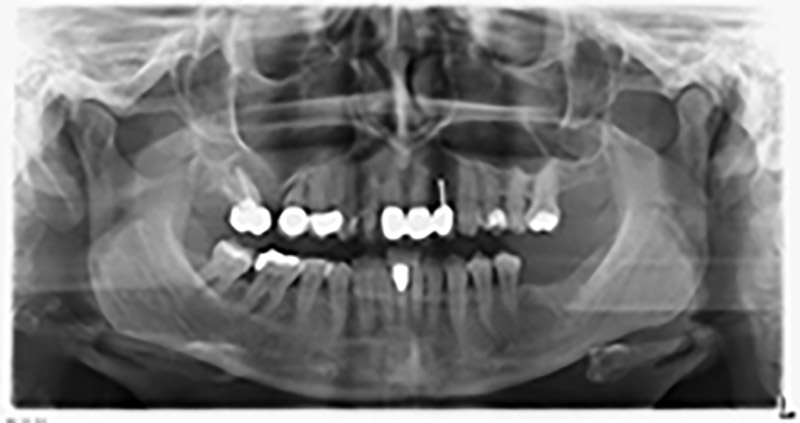

About six months after teeth 16 and 14 were extracted, a digital volume tomography (DVT, Planmeca) examination was performed for planning and risk minimization purposes. It clearly showed that the bone had not regenerated to the desired volume (Fig. 2 to 7).